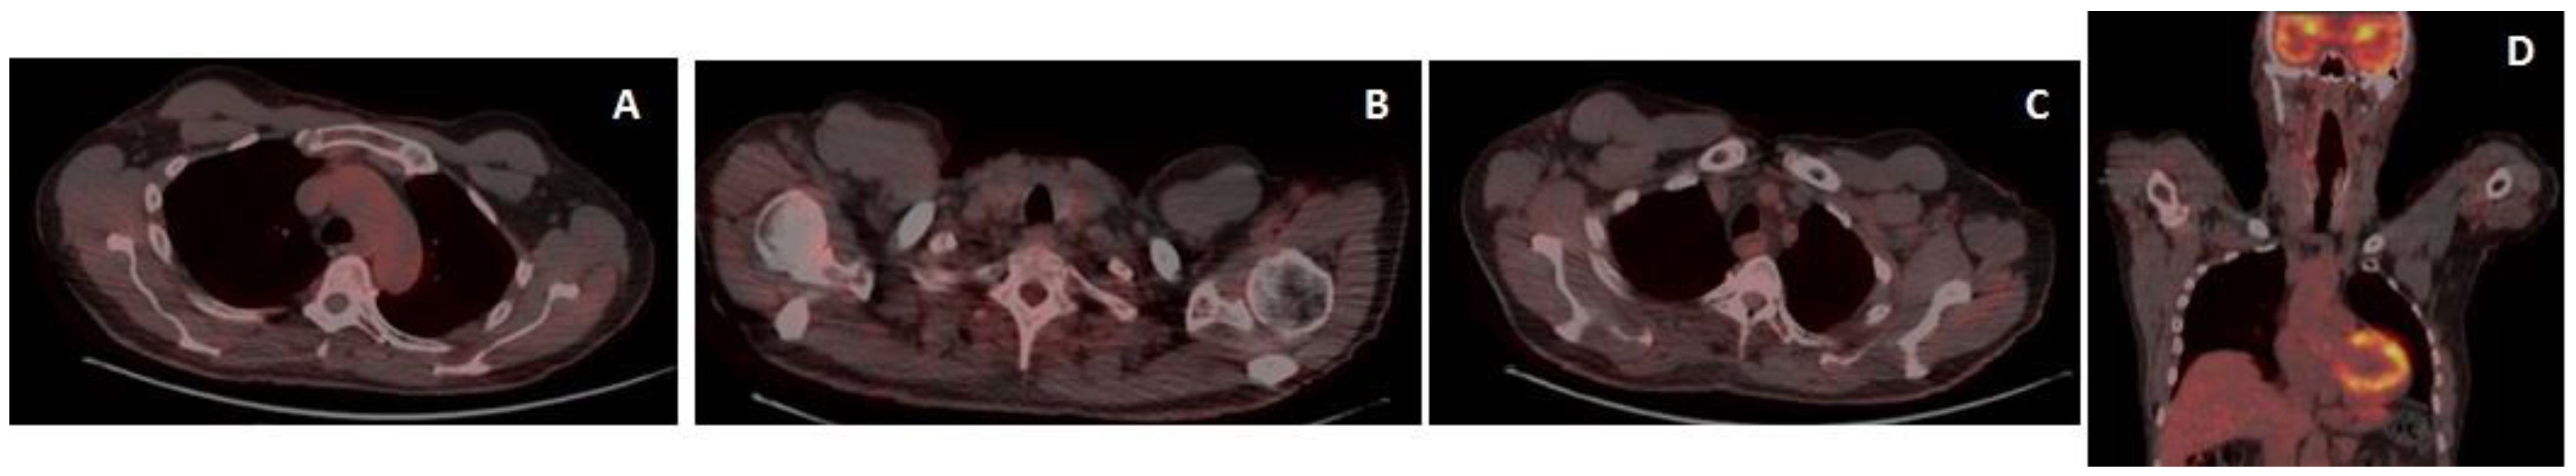

18F-Fluorodeoxyglucose positron emission tomography/CT (18-FDG-PET/CT) showed increased tracer uptake in the right axillary adenopathy, in the right supraclavicular adenopathy and in multiple axillary adenopathies (Figure 5).

Figure 5.

18-FDG-PET/CT at baseline (axial and coronal sections), increased tracer uptake in the right axillary adenopathy mass (SUV max 9.7) (A), in the right supraclavicular adenopathy (SUV max 7.6) (B) and in multiple axillary adenopathies (level I–III) (C,D).